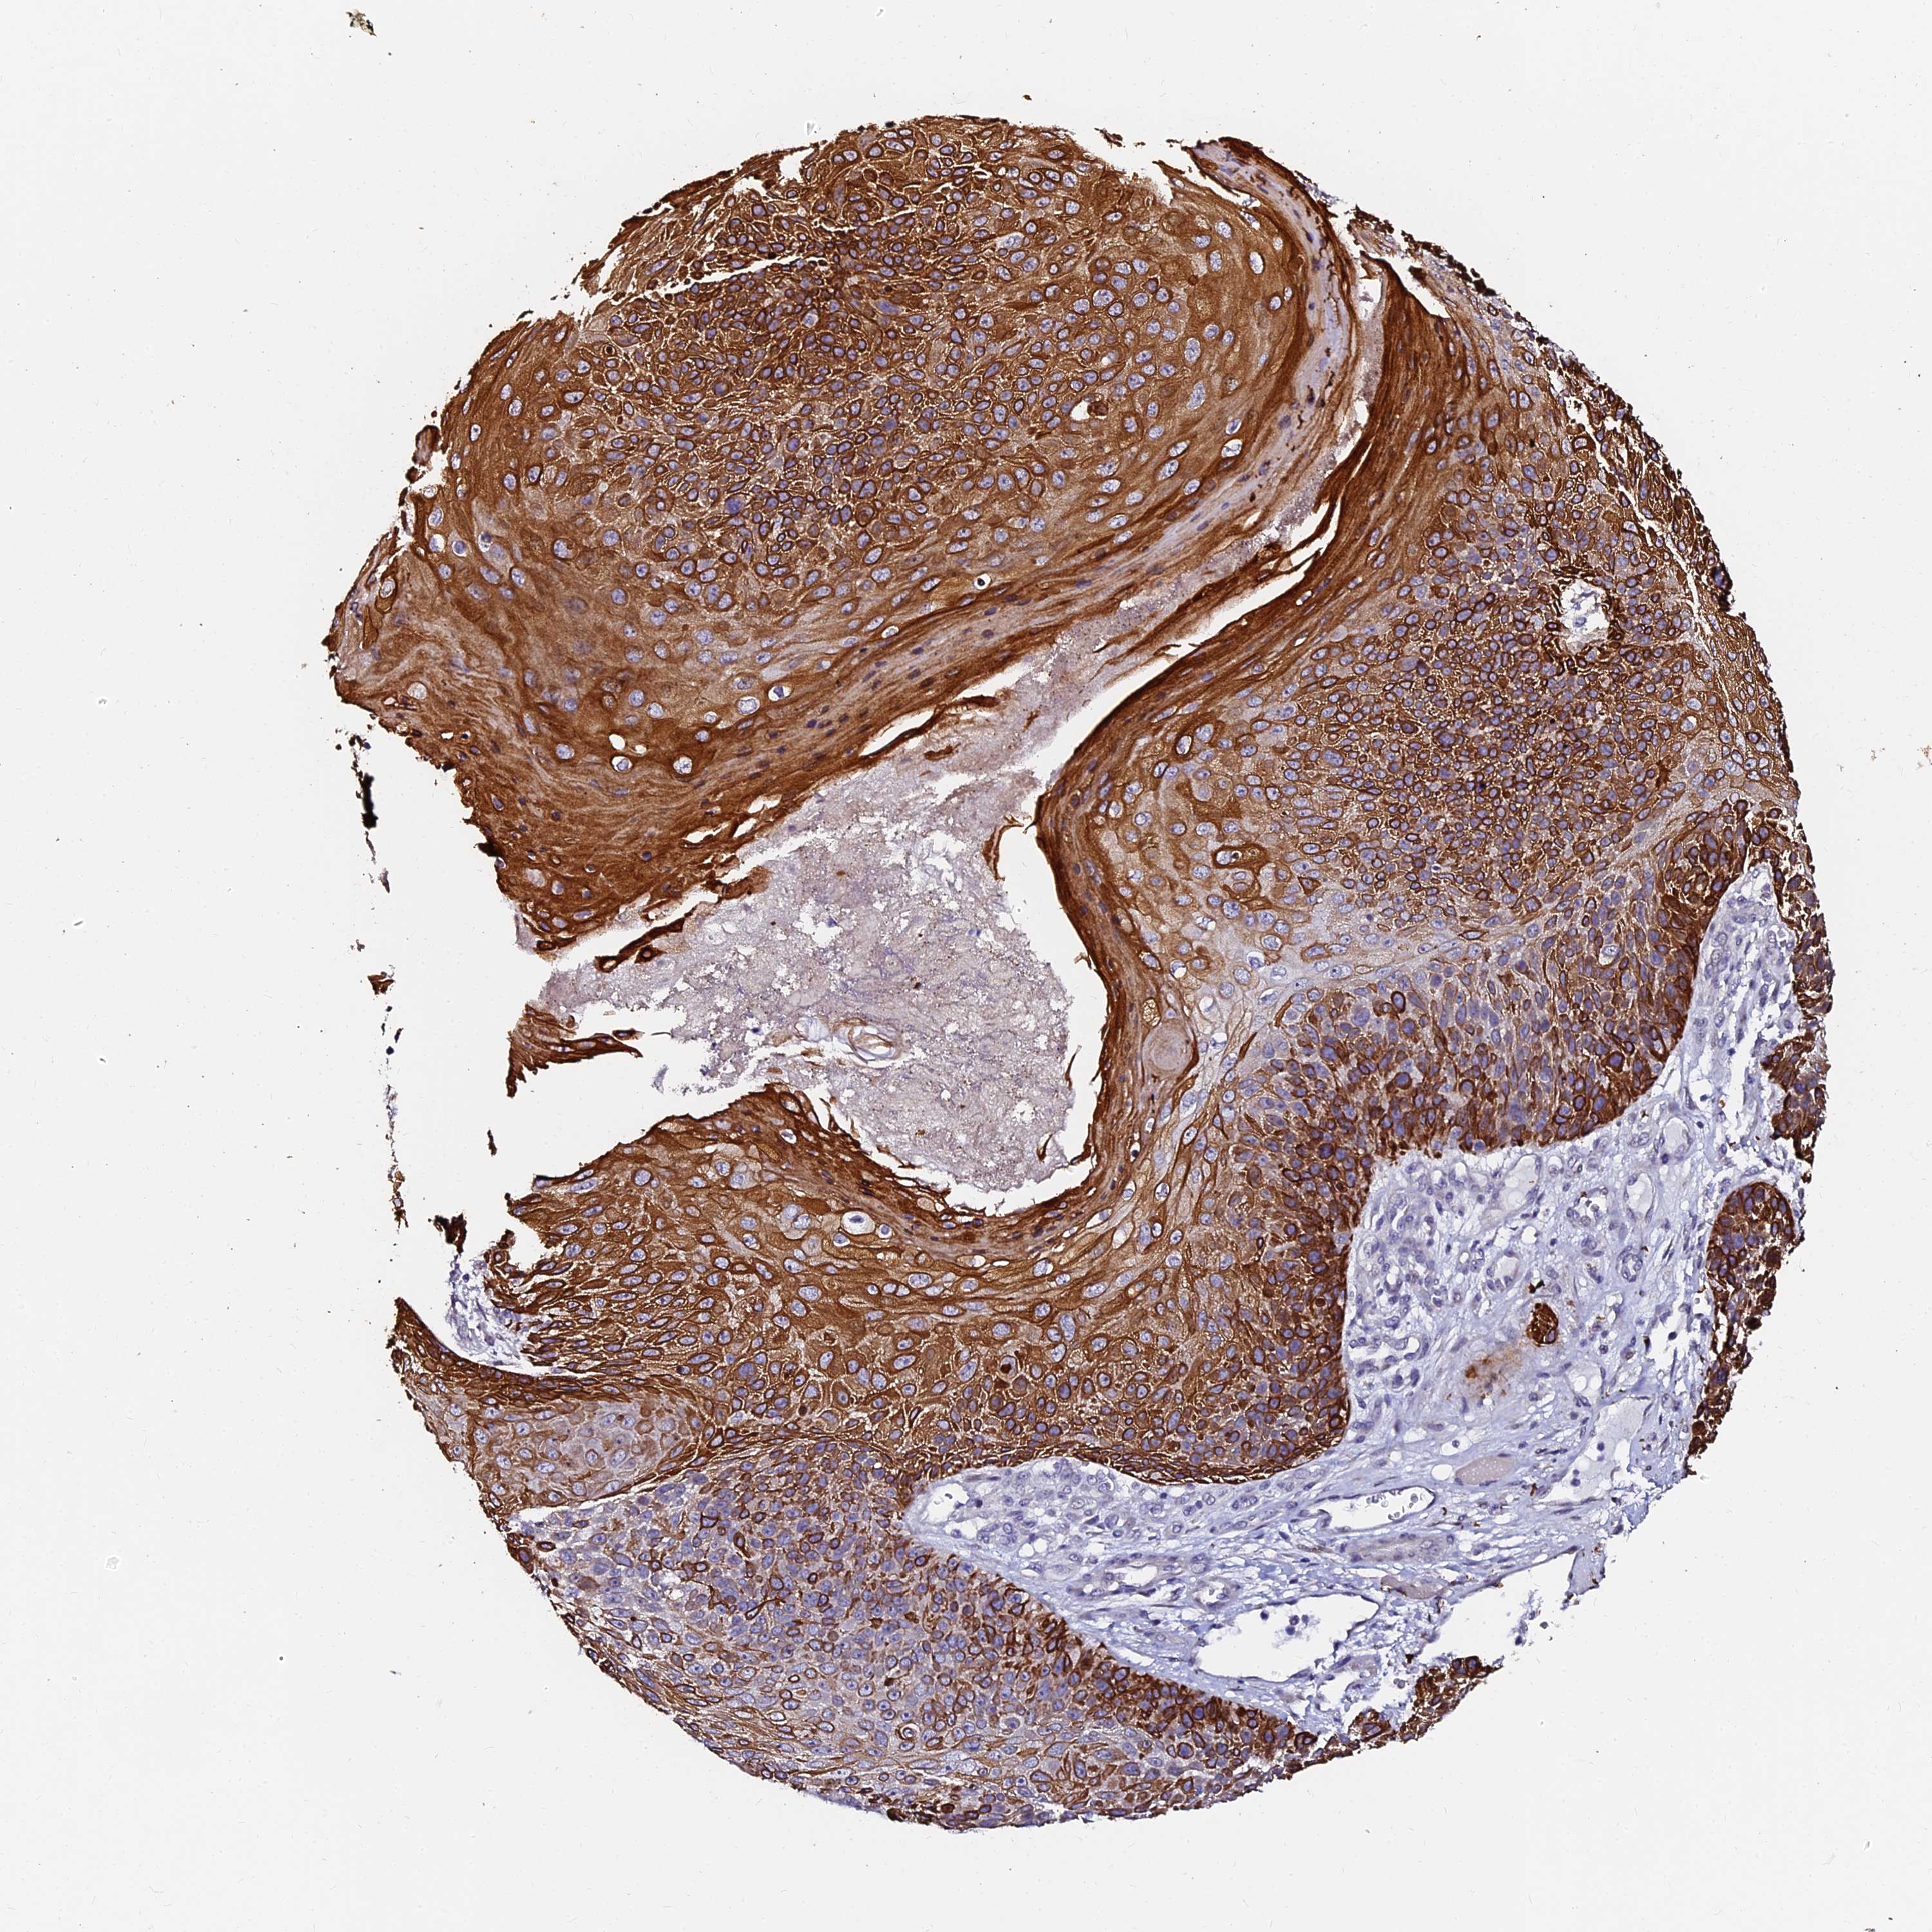

SKIN CANCER - Protein expressioni

A mouse-over function shows sample information and annotation data. Click on an image to view it in a full screen mode. Samples can be filtered based on level of antibody staining by selecting one or several of the following categories: high, medium, low and not detected. The assay and annotation is described here.

Each image is clickable and will lead to virtual microscopy that enables deeper exploration of all samples and also displays staining intensity scores, fraction scores and subcellular localization as well as patient and tissue information for each sample.

Antibody HPA039764

Staining

High

Intensity

Strong

Quantity

>75%

Location

Nuclear

Basal cell carcinoma

Squamous cell carcinoma, NOS

Squamous cell carcinoma, metastatic, NOS

Squamous cell carcinoma in situ, NOS